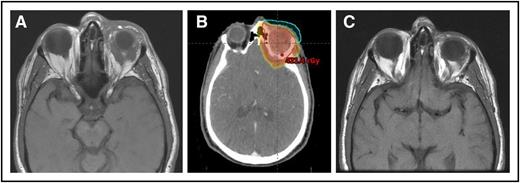

(A) A 64-year-old man with MZL of the left orbit. (B) An intensity-modulated RT plan of 24 Gy was designed, but only 4 Gy was delivered with near-CR obtained. (C) Seven months’ follow-up after only 4 Gy with no progression.

Advances in tumor imaging and radiation treatment planning, targeting, and delivery as well as a larger menu of RT systems (including intensity-modulated RT, electrons, and protons) provide an opportunity for more conformal treatment and a possibility of safely reducing the irradiated volume in the orbit in selected cases, particularly when the MZL is limited to the conjunctiva or lacrimal gland. Yet, the standard recommendation for most cases is to still include the full orbital contents unless the disease is confined to the conjunctiva (see figure).